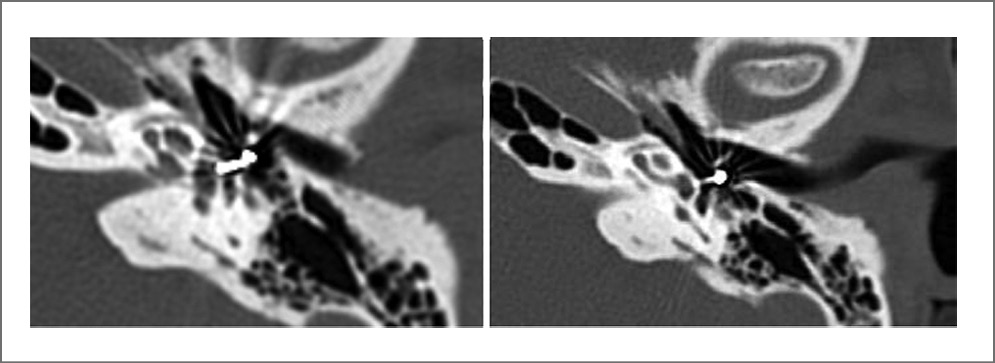

На КТ височных костей после хирургического лечения с разницей в 1–3 года визуализировался установленный стапедиальный протез. Проведено сравнение данных КТ у пациентов с титановыми и нитиноловыми протезами. Только в группе с установленными нитиноловыми протезами удалось оценить положение его на длинной ножке наковальни, в области преддверия, целостность длинной ножки наковальни (что указывало на отсутствие ее асептического некроза) в связи с отсутствием артефактов (рис. 5, 6).

Рис. 5. КТ височных костей у пациента с установленным SE NiTiNOL.

Рис. 6. КТ височных костей у пациента с установленным Ti/PTFE.

Помимо этого экспериментально на 8 кадаверных височных костях (по 4 в каждом из двух исследований) проведено сравнение данных КТ, полученных при установке титановых и нитиноловых протезов, и определена возможность визуализации области крепления кольца протеза. В результате оказалось, что в 4 случаях с установкой нитинолового протеза отсутствуют артефакты, что позволяло визуализировать кольцо крепления протеза; в других 4 случаях с титановым протезом этого выявить не представлялось возможным (рис. 7).

Рис. 7. КТ, на котором представлена визуализация кольца крепления протеза.